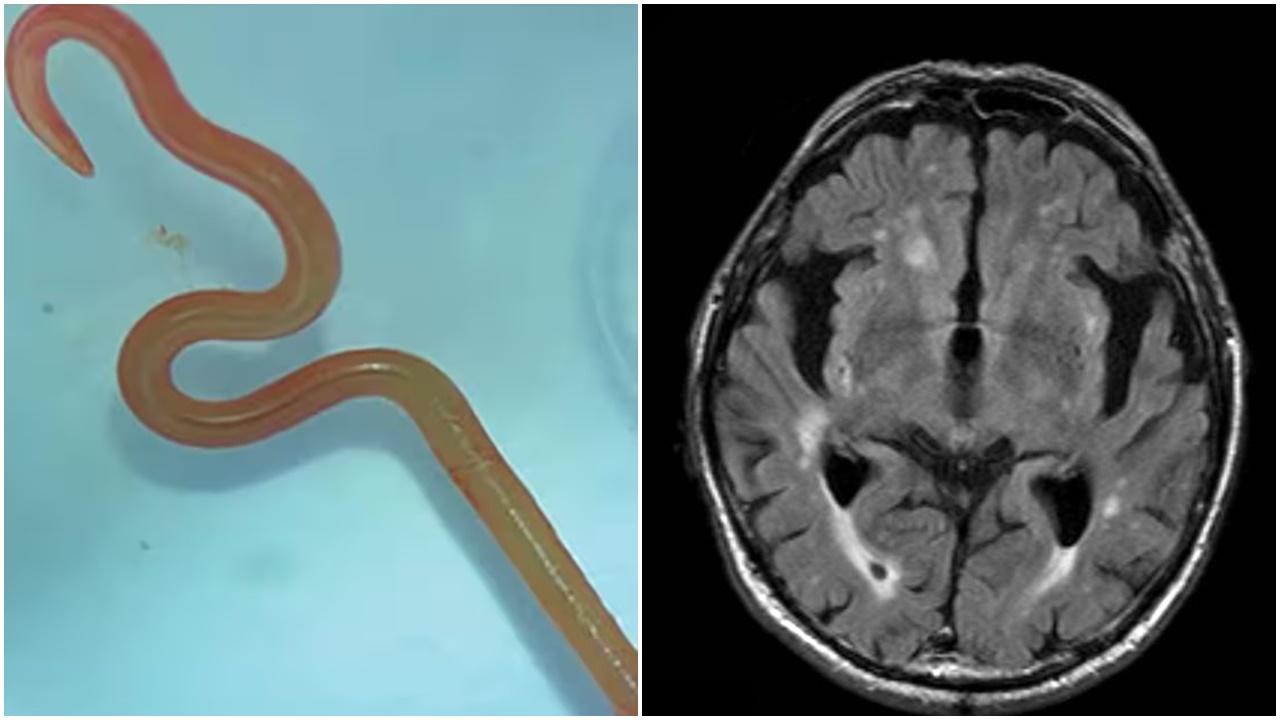

• 男子釣魚突抽搐失語,開腦驚見10厘米活蟲蠕動。(微博)

男子釣魚突抽搐失語 開腦驚見10厘米活蟲蠕動(有片)

• 大腦取出8厘米長寄生蟲,醫生:還在蠕動。(X)

毛管戙|大腦取出8厘米長寄生蟲 醫生都驚:還在蠕動